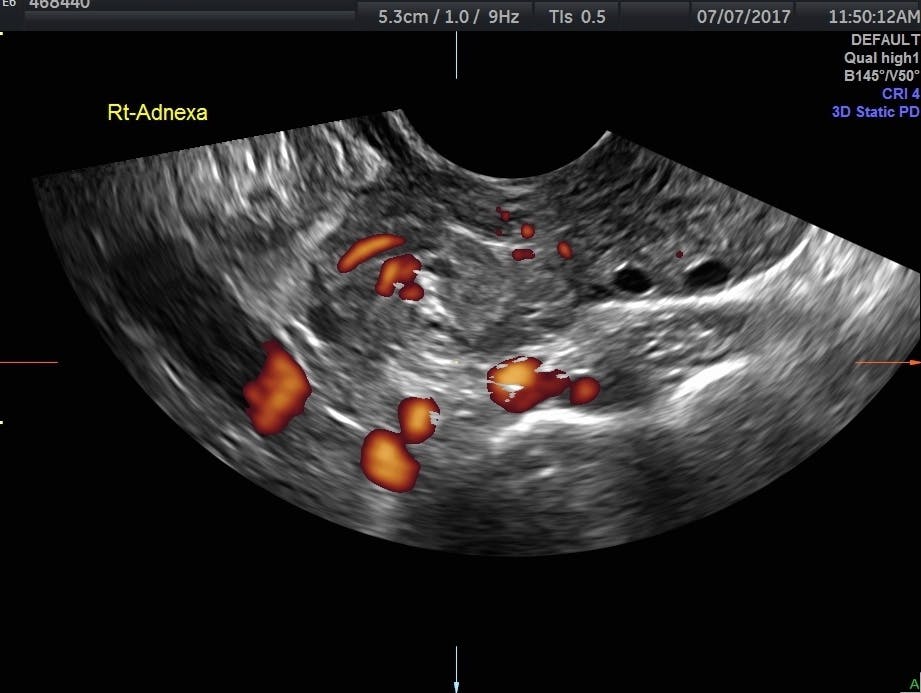

Transvaginal Ultrasonography And Female Infertility Glowm

Transvaginal Ultrasonography And Female Infertility Glowm from resources.ama.uk.com

Aug 26, 2020 · a severe pelvic infection. The pain is usually sharp and most often on the lower right side. Occasionally they may produce bloating, lower abdominal pain, or lower back pain. Some women develop less common types of cysts that a doctor finds during a pelvic exam. This may result in vomiting or feeling faint.and even cause head aches. Treatment depends upon the cause and type of cyst. The majority of cysts are harmless. Ovarian cysts are usually diagnosed by ultrasound, ct scan, or mri, and correlated with clinical presentation and endocrinologic tests as appropriate. Jul 21, 2021 · rarely, some ovarian cysts make abnormal amounts of female (or male) chemicals (hormones) which can cause unusual symptoms. If the cyst either breaks open or causes twisting of the ovary, it may cause severe pain. Often they cause no symptoms. Ovaries are female reproductive organs. It often forms during or after ovulation.

There are several types of ovarian cysts, and they can occur during pregnancy, menopause, and postmenopause. Cystic ovarian masses that develop after menopause might be cancerous (malignant). Occasionally they may produce bloating, lower abdominal pain, or lower back pain. If it is smaller than 2 inches (5 cm) in diameter it may very well go away on its own. An ovarian cyst (oh vair ee uh n sist) is a fluid filled sac in or on the surface of an ovary. One ovary is located on each side of the uterus in the abdomen (picture 1). But some cysts, such as endometriomas, could be on either side. Treatment depends upon the cause and type of cyst. If the cyst is smooth and completely filled with clear fluid, chances are it is not too dangerous. It often forms during or after ovulation. Ovarian cysts are usually diagnosed by ultrasound, ct scan, or mri, and correlated with clinical presentation and endocrinologic tests as appropriate. Some women develop less common types of cysts that a doctor finds during a pelvic exam. If a male sonographer is doing the scan, there will need to be a female chaperone present for the transvaginal or translabial portion of the exam.

In these cases, you may have: If the infection spreads to the ovaries, it can cause cysts. This may result in vomiting or feeling faint.and even cause head aches. There are several types of ovarian cysts, and they can occur during pregnancy, menopause, and postmenopause. The pain is usually sharp and most often on the lower right side. But some cysts, such as endometriomas, could be on either side. One ovary is located on each side of the uterus in the abdomen (picture 1). Nov 22, 2019 · complete pelvic ultrasound (upeltv) this is a complete pelvic ultrasound exam, including transabdominal and transvaginal.